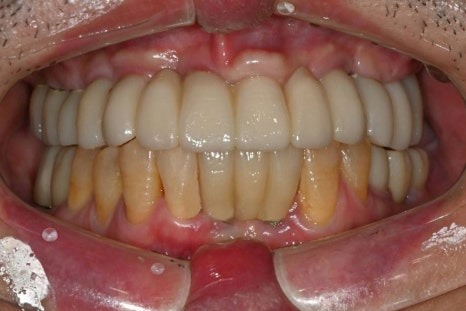

수술 후 4개월

수술 후 6개월 후 보철완료

치료 전 / 치료 후